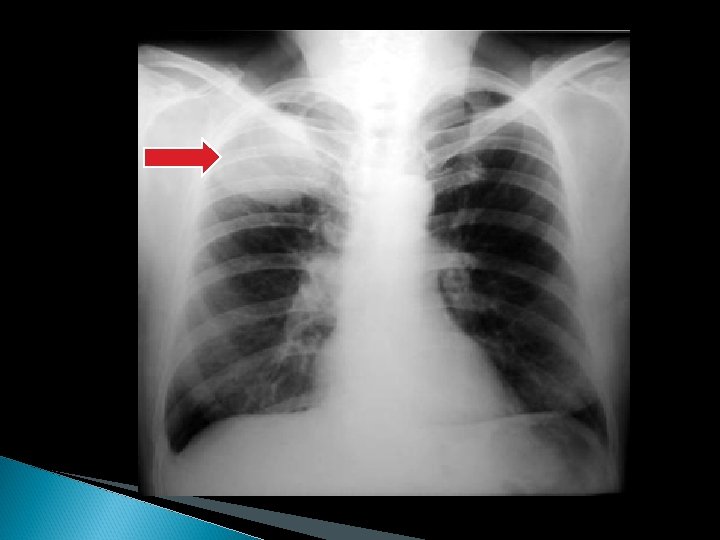

METODOS DE IMAGEN RX DE TORAX: Sigue siendo el procedimiento básico mas importante y tiene una eficacia global del 7088% para diagnostico de sospecha de la enfermedad. En un 5 -15% de los casos antes de aparecer los síntomas el único dato que permite sospechar la existencia de un CP es la presencia de alguna anormalidad en la misma.

Manifestaciones radiológicas: 1: - Anormalidades en región hiliar con aumento o prominencia de la densidad hiliar. 2: - Alteraciones del parenquima pulmonar: Nodulo (menor o igual de 4 cms), Masa (mayor de 4 cms), Masas multiples, Evidencia de obstrucción bronquial (colapso). . . 3: - Alteraciones de las estructuras intratorácicas extrapulmonares: ensanchamiento o masa mediastinica, erosion o destruccion de costillas o vertebras, derrame pleural y elevacion diafragmatica.